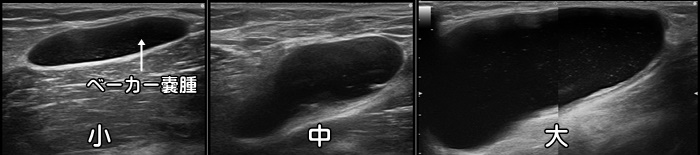

ベーカー嚢腫

膝の裏側の内側にピンポン玉のような“しこり”があればベーカー嚢腫を疑います。

中年以降の女性に好発します。小さいものから大きいものまで様々です。

症状が無ければ治療の必要はありませんが、神経鞘腫など他の腫瘍との鑑別が必要です。